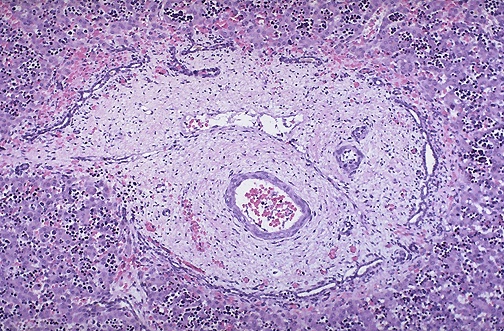

| You're right, this isn't kidney, but remember that autosomal recessive polycystic kidney disease also manifests with congenital hepatic fibrosis, as seen here in which a portal area is expanded with increased bile ducts radially arranged around the perimeter. The abnormal fibrocysin protein product of the mutated PKHD1 gene affects liver and pancreas as well as kidney. The many dark clusters of cells in the hepatic parenchyma are islands of extramedullary hematopoiesis typical for fetal liver. |